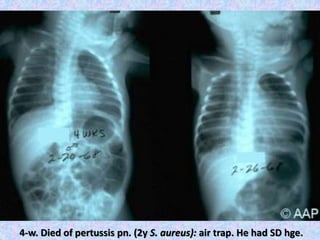

4w-old: pertussis pn. with air trapping & collapse

(segmental/lobar collapse not uncommon)

4-w. Died of pertussis pn. (2y S. aureus): air trap. He had SD hge.